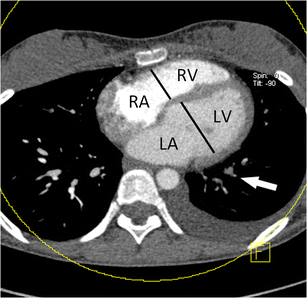

Fig. 1